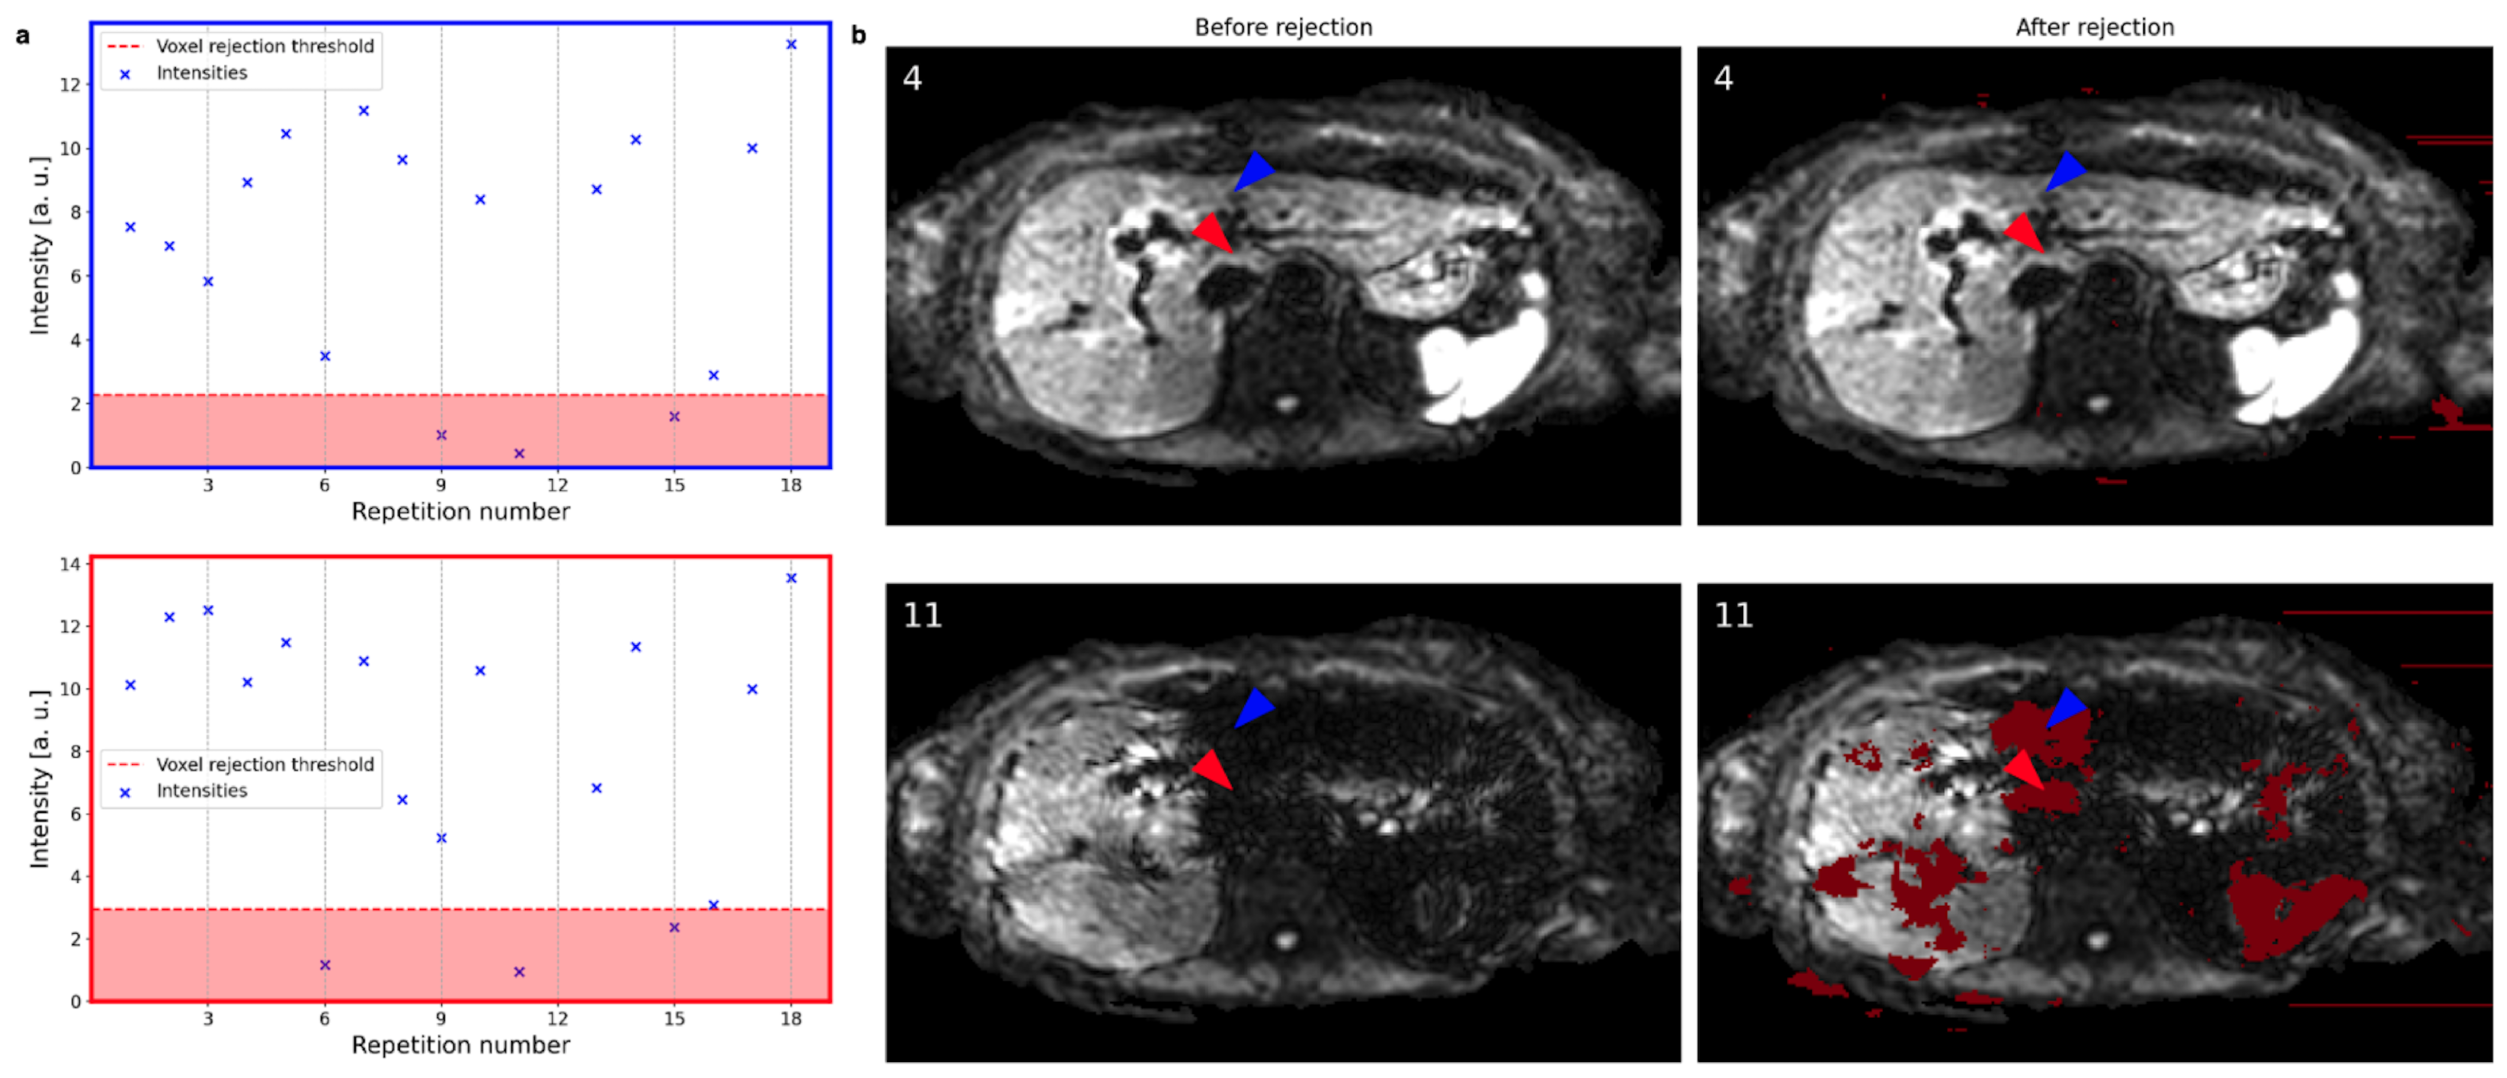

3.1. Repetition and Voxel Rejection